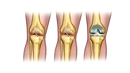

Sağ Diz Kapağı Ağrısı: Belirtileri ve TedavisiDiz kapağı, vücudun en karmaşık eklemlerinden biri olup, günlük yaşamda önemli bir rol oynamaktadır. Sağ diz kapağında meydana gelen ağrı, birçok insanda yaygın bir sorundur ve çeşitli nedenlerden kaynaklanabilir. Bu makalede, sağ diz kapağı ağrısının belirtileri, olası nedenleri ve tedavi yöntemleri detaylı bir şekilde ele alınacaktır. BelirtilerSağ diz kapağı ağrısının belirtileri kişiden kişiye değişiklik gösterebilir. Ancak genellikle aşağıdaki belirtiler gözlemlenmektedir:

NedenlerSağ diz kapağı ağrısının birçok olası nedeni bulunmaktadır. Bu nedenler arasında şunlar yer alır:

Tedavi YöntemleriSağ diz kapağı ağrısının tedavi yöntemleri, ağrının nedenine bağlı olarak değişiklik göstermektedir. Tedavi yöntemleri arasında: